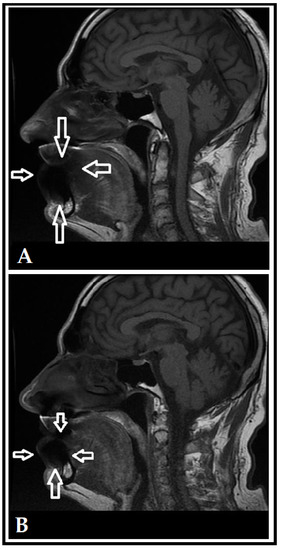

- Flügge, T.; Ludwig, U.; Amrein, P.; Kernen, F.; Vach, K.; Maier, J.; Nelson, K. MRI for the display of autologous onlay bone grafts during early healing—An experimental study. Dentomax. Radiol. 2020, 50, e2020068. [Google Scholar] [CrossRef]

- Wanner, L.; Ludwig, U.; Hövener, J.B.; Nelson, K.; Flügge, T. Magnetic resonance imaging—A diagnostic tool for postoperative evaluation of dental implants: A case report. Oral Surg. Oral Med. Oral Pathol. Oral Radiol. 2018, 125, e103–e107. [Google Scholar] [CrossRef] [PubMed]